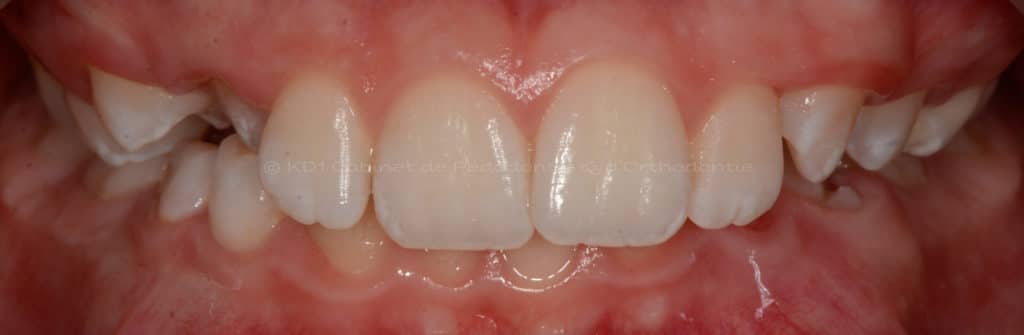

Cas #1 – Traitement avec des bagues, deuxièmes prémolaires et dent de sagesse supérieures ectopiques.